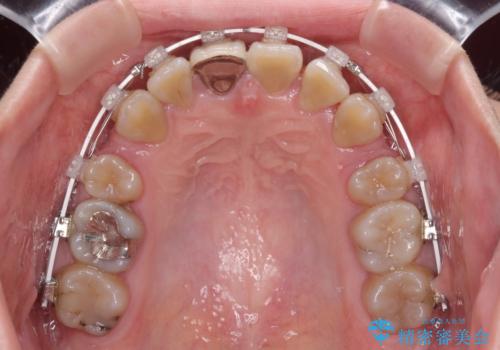

八重歯とクロスバイト 目立たないワイヤー装置での抜歯矯正

- 八重歯や前歯のデコボコを気にして来院された患者様です。

歯列が前方に傾斜しており、デコボコが強かったため、上下左右第一小臼歯4歯を抜去し、ワイヤー装置による矯正治療を行うこととしました。

上下の正中がずれていましたが、抜歯矯正であったので、極力正中位置を合わせるように治療を進めて行きました。

顎間ゴムの使用などにより、正中位置を改善することができました。